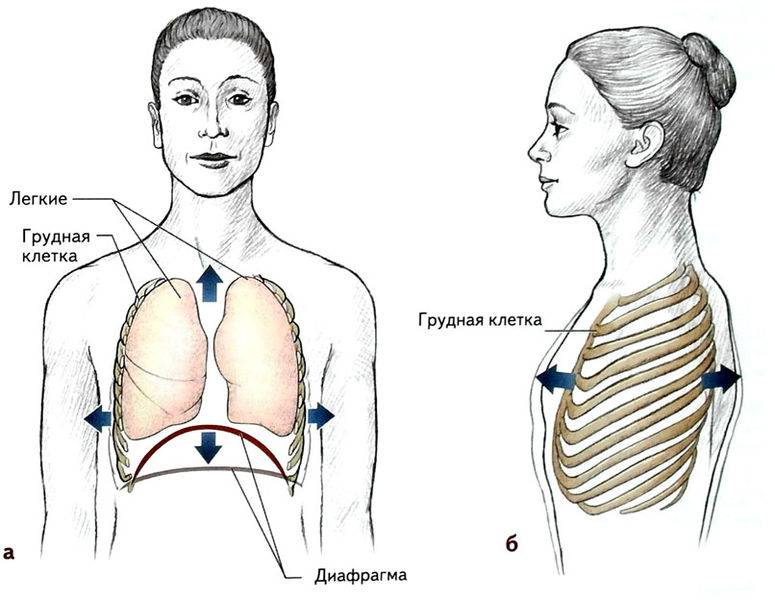

При любом типе дыхания за обработку кислорода отвечают легкие. Но их увеличение, как и изменение объема полости груди, зависит от 2 разных способов:

- При вдохе стенка груди приподнимается и отодвигается от позвоночника, из-за чего полость грудной клетки спереди увеличивается (образуется дополнительный объем между позвоночником и грудиной). В этом процессе участвуют ребра, прикрепленные к позвоночнику под острым углом. Своими концами они формируют дугу, расширяя возможный объем. Так как ребра крепятся к грудной кости, они тянут ее за собой.

- Второй способ зависит от опущения грудобрюшной преграды по направлению книзу. Это – диафрагма, имеющая куполообразную форму. Грудные мышцы отвечают в процессе дыхания за то, чтобы этот купол тянулся вниз, освобождая простор для легких. Середина опускается книзу и создается нужный объем. Из-за опущения грудная часть диафрагмы давит на живот, в результате выпячивается его стенка.

Главный орган в брюшном дыхании — диафрагма. Диафрагмальная мышца — это куполообразная перегородка, она отделяет грудную клетку от органов, расположенных ниже в брюшной полости. На вдохе диафрагмальная мышца идёт вниз и сжимается, заставляя брюшную стенку выдвигаться вперёд. В момент выдоха диафрагмальная мышца возвращается вверх и приобретает форму купола, выгоняя воздух из лёгких.

На вдохе диафрагма движется вниз, на выдохе — поднимается вверх